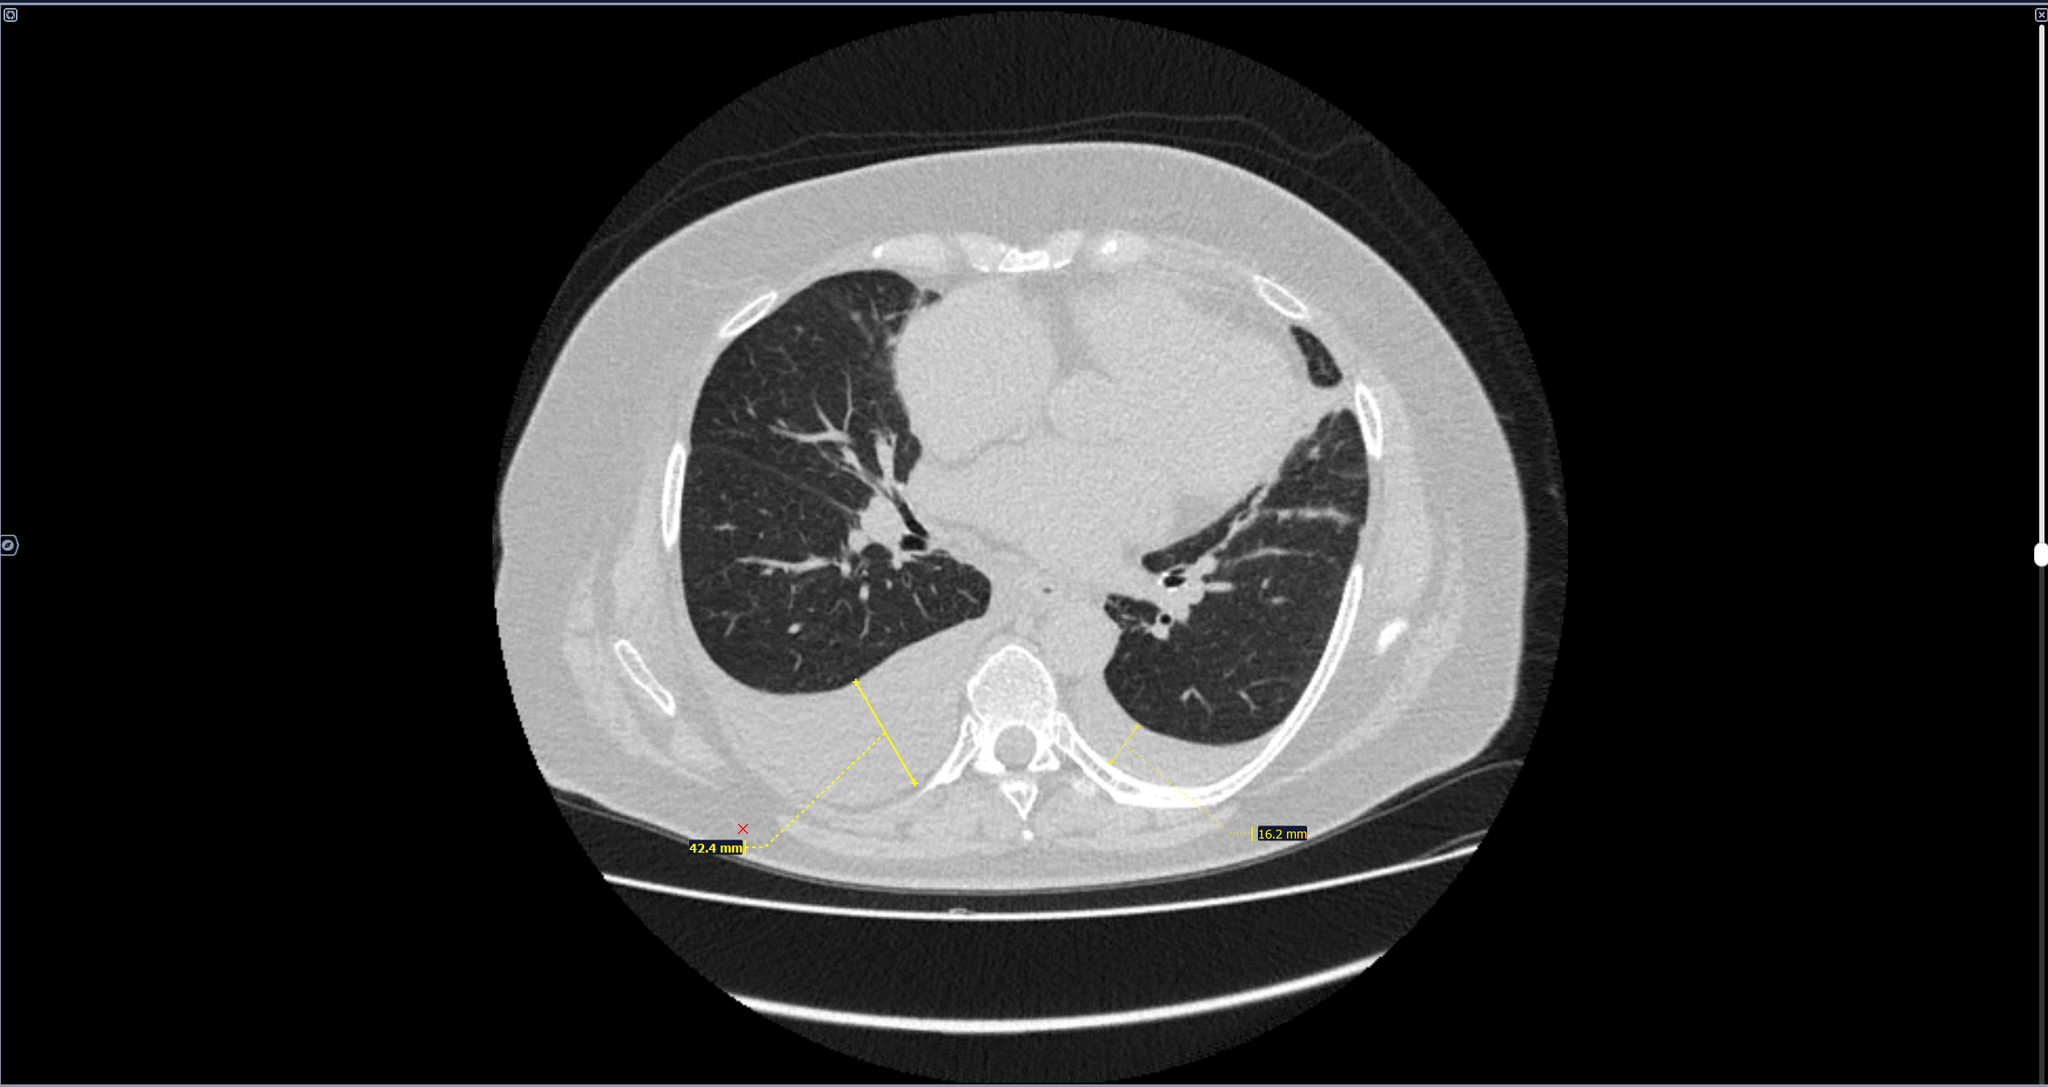

Двустороннее ассиметричное скопление жидкости плотностью +10-20 HU,с максимальной толщиной выпота справа -42мм,слева-16мм(ориентировочный объем жидкости справа-530мл,слева-157мл).

Заключение: Двусторонний гидроторакс, средний по объему-справа, малый-слева.